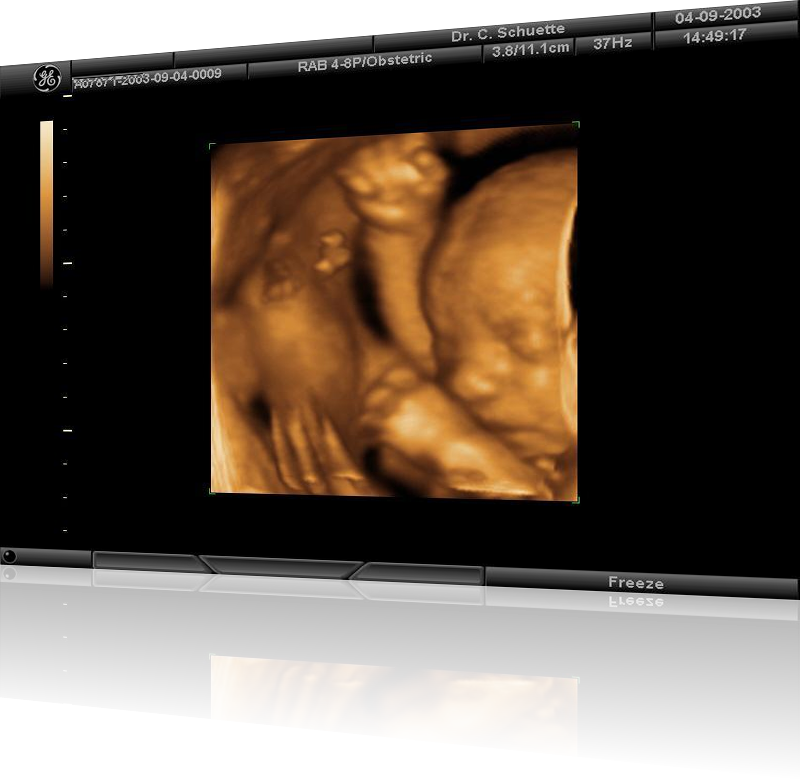

• 3D / 4D Ultraschall ermöglicht verblüffend fotorealistische Bilder, sogar Gestik und Mimik können in bewegten Sequenzen (4D) festgehalten werden